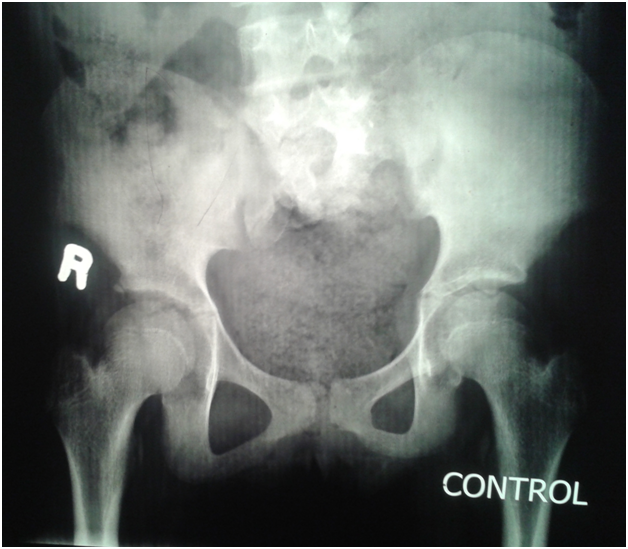

An eleven year old girl was presented to with chronic constipation, persistent dribbling of urine and recurrent urinary tract infections since early childhood. She received treatment by local physicians but remained without proper response. On examination, child was a febrile and her bladder was palpable. Her buttocks were flattened (Figure 1) and external genitalia were wet and excoriated. Anal tone was found decreased on digital rectal examination and the rectum was loaded with hard stool. No definite neurological deficit was found. She was catheterised and stool evacuated with per rectal enema. Her blood analysis showed low haemoglobin (8.1gm %), leucocytosis and raised serum creatinine level (2.2mg %). Urine analysis showed plenty of pus cells and growth of E. coli. Ultrasonography suggested bilateral hydro uretoronephrosis (rt>>lt) with loss of cortico medullary differentiation on right kidney and thickened irregular bladder with significant post void residual urine. Tc-99m DTPA renogram shows poorly functioning right kidney and satisfactorily functioning left kidney. Complete sacral agenesis, 5th lumbar vertebral atrophy and scoliosis with convexity towards right side seen in the control film (Figure 2) while neurogenic bladder with bilateral grade V vesico- ureteric reflux revealed on Voiding phase cystourethrogram (Figure 3). Child was further evaluated with urodynamic study, which suggested an overactive bladder in filling phase (Figure 4). Repeat blood analysis shows (Figure 4) normalisation of serum creatinine (1.2mg %). Her catheter has been removed and she has been placed on self clean intermittent catheterisation along with anti cholinergic (oxy butinine 5mg/daily) and laxative.

Figure 1 Showing flattening of the buttock.

Figure 2 Complete Sacral agenesis, 5th lumbar vertebral atrophy.

Figure 3 Complete Sacral agenesis, 5th lumbar vertebral atrophy

Present report is a neglected case of sacral agenesis who presented late at 11years of age. Constipation and urinary incontinence was main complaint and on evaluation she found to have type III sacral agenesis, overactive bladder with bilateral reflux disease leading to kidney injury. High index of suspicion and some clinical clues like flattened buttock and short gluteal folds,9 are helpful for early diagnosis to avoid social stigma of urinary incontinence and to prevent kidney injury.